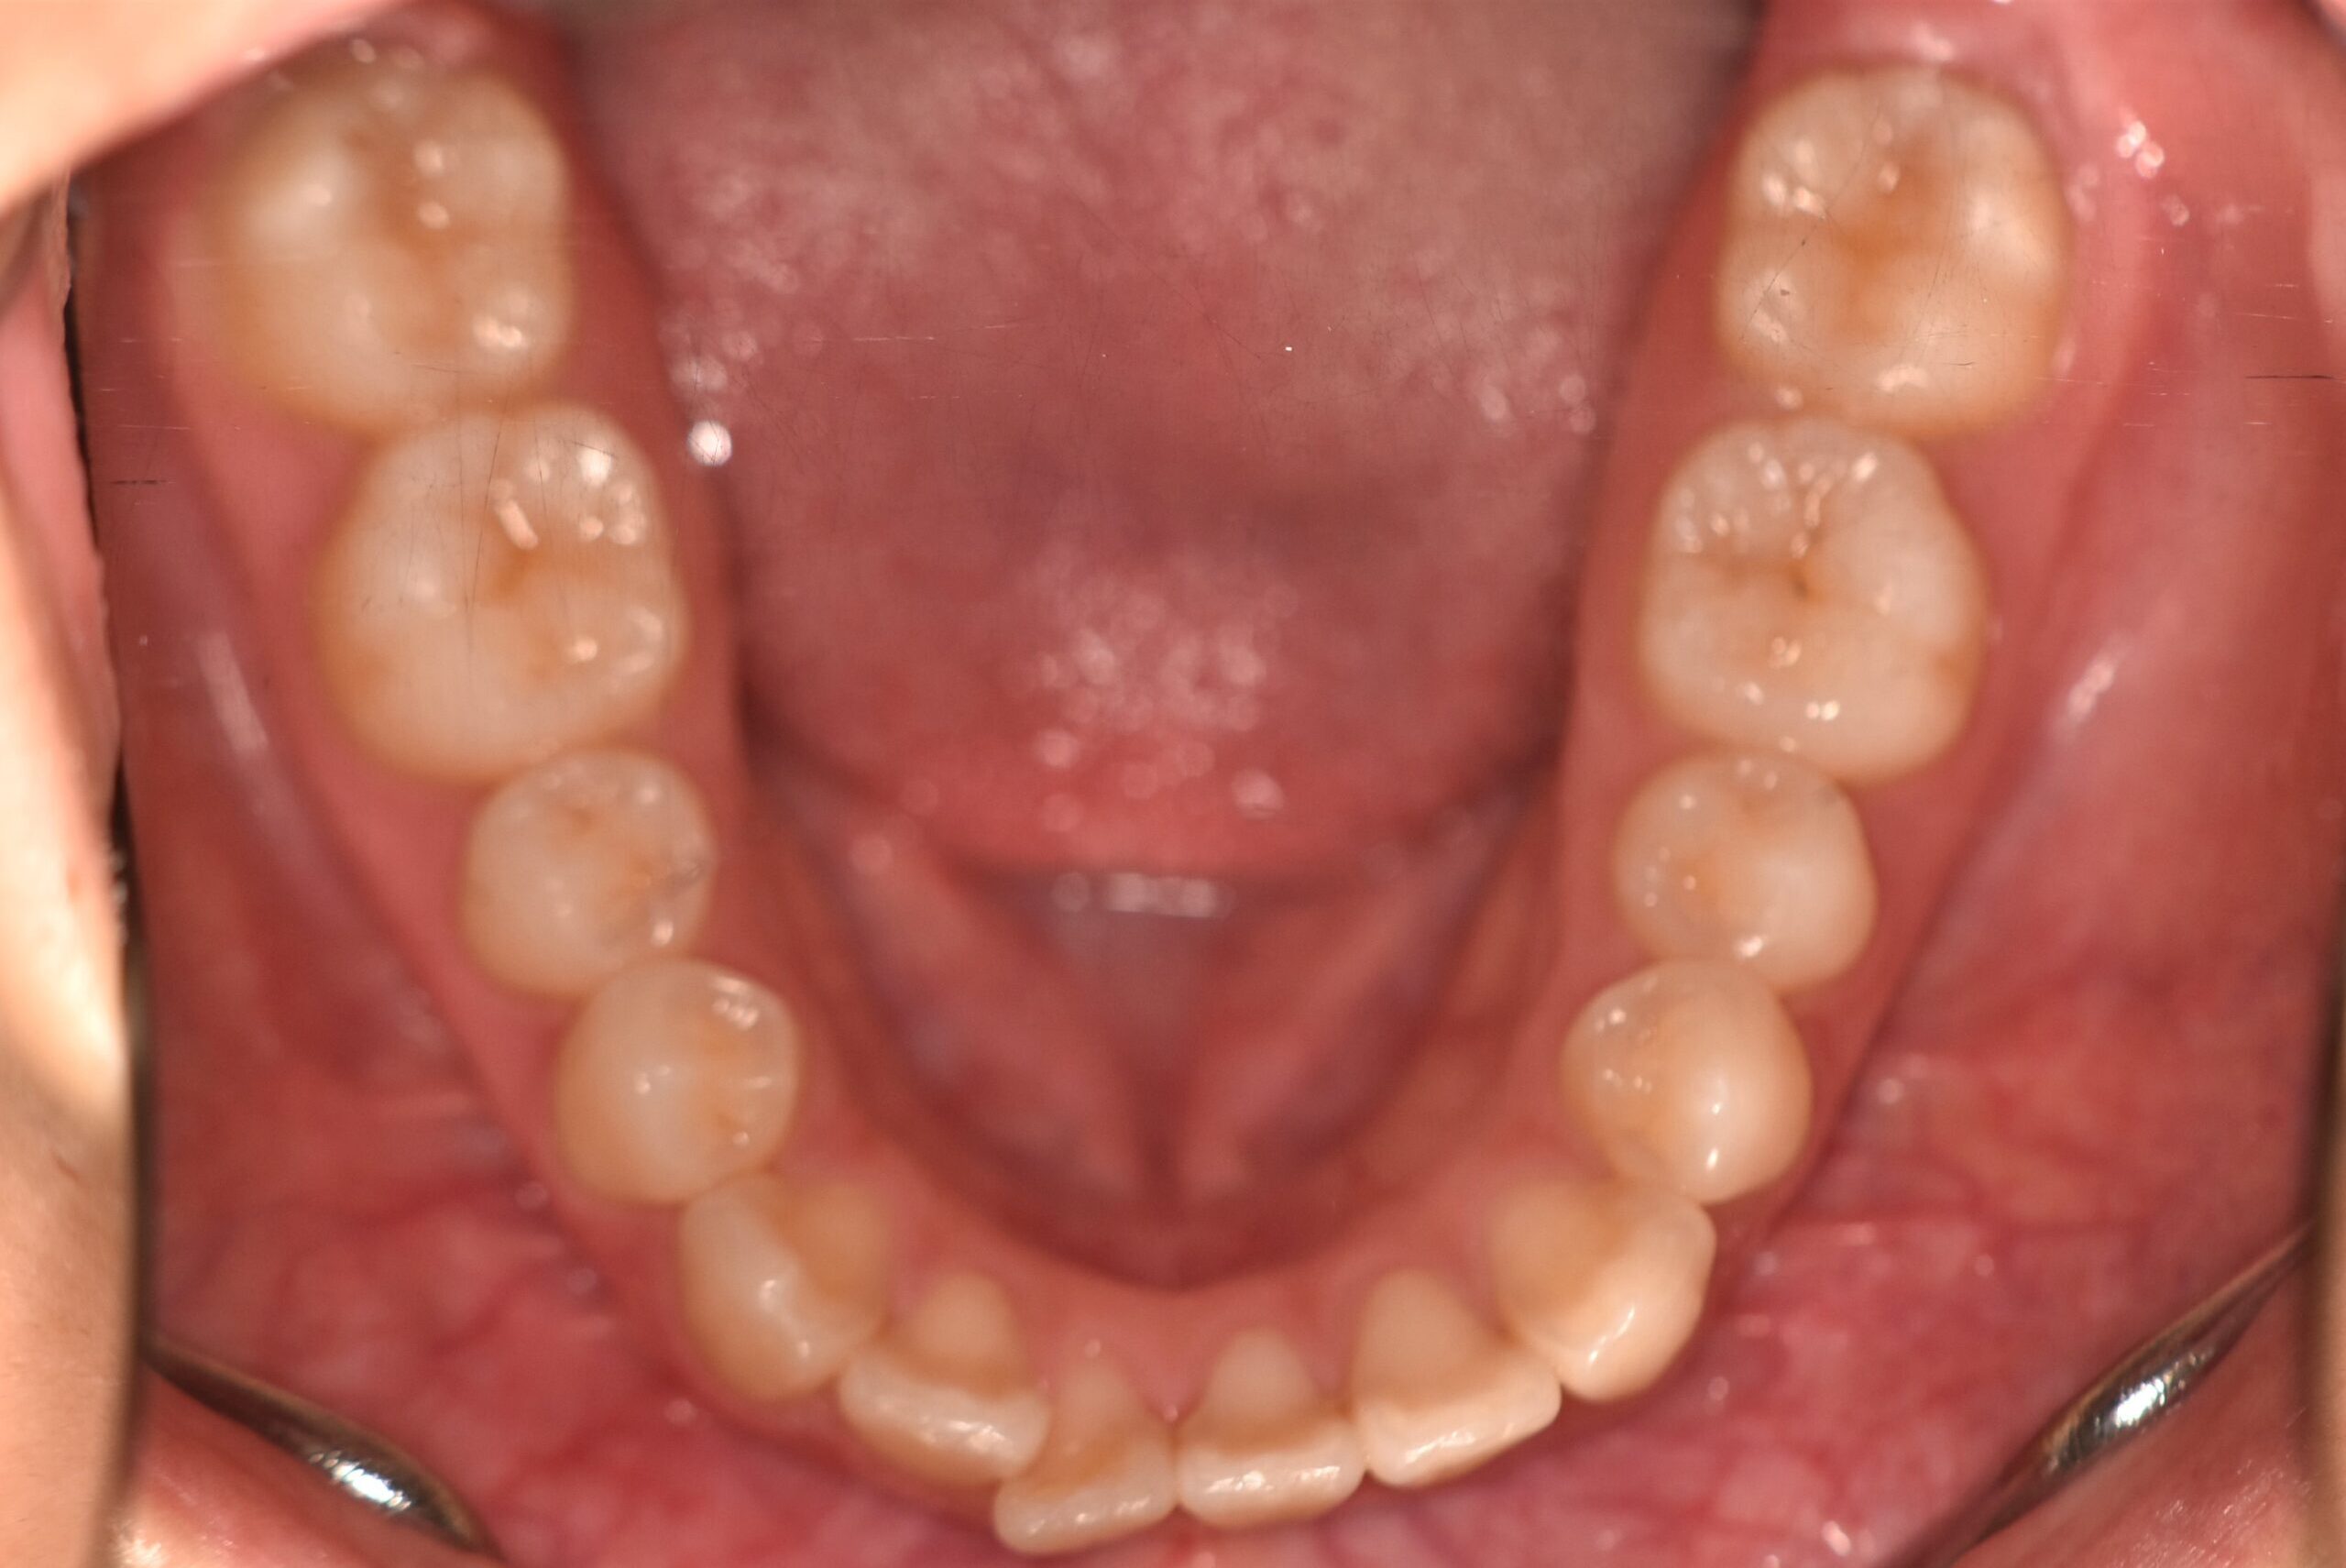

叢生(非抜歯)[2704]

初診時

年齢

17歳11ヶ月 性 別 女性

治療期間 1年10ヶ月 費 用 矯正施術料:900,000円 調整料:5,000円

治療内容の詳細 初診時17歳の女性で、かみ合わせが悪く少しガタガタしていることをを気にされ来院されました。

検査の結果、上下顎叢生を伴うアングル1級不正咬合と診断しました。

治療としては、非抜歯の上、マウスピース型矯正装置(インビザライン)で歯の配列を行いました。

治療期間は、1年10ヶ月でした。